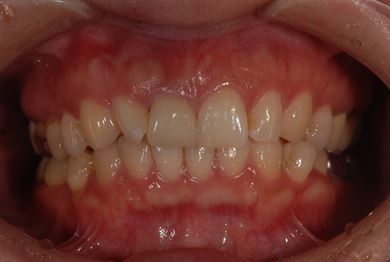

| 性別/年齢 | 女性 / 38歳 | ||||||||||||||||||||||||||||||||

| 主訴 | 右奥歯2本、インレーの相談をしたい。 | ||||||||||||||||||||||||||||||||

| 治療方針 | セラミック治療にて、審美的回復を行う。 | ||||||||||||||||||||||||||||||||

| 治療内容 | ハイブリッドセラミックインレー2本、メタルボンドセラミッククラウン2本(メタルボンド用土台2本)、オールセラミッククラウン1本(オールセラミック用土台1本) | ||||||||||||||||||||||||||||||||

| 総治療費 | 495,758円 | ||||||||||||||||||||||||||||||||

| 治療期間 | 1年6ヶ月 |